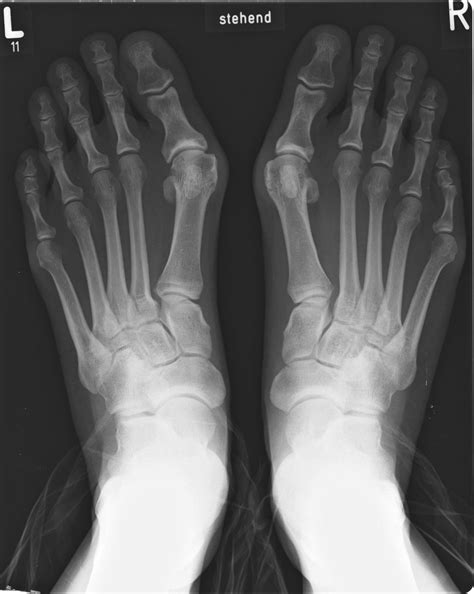

The Role of Weight-Bearing Imaging

One critical aspect of a Bunion X Ray is the weight-bearing requirement. Many patients ask why they cannot simply lie down for the scan. When you lie down, the soft tissues relax, and the skeletal structure may appear more aligned than it actually is when you are walking. By standing, the gravitational force mimics the stress placed on your feet during your daily activities. This allows the doctor to see the true extent of the deformity and how it impacts your foot mechanics.

In addition to the standard top-down view, doctors may also order a lateral view or an oblique view. These extra angles help assess if there is a rotation of the big toe, which is a common component of progressive bunions.